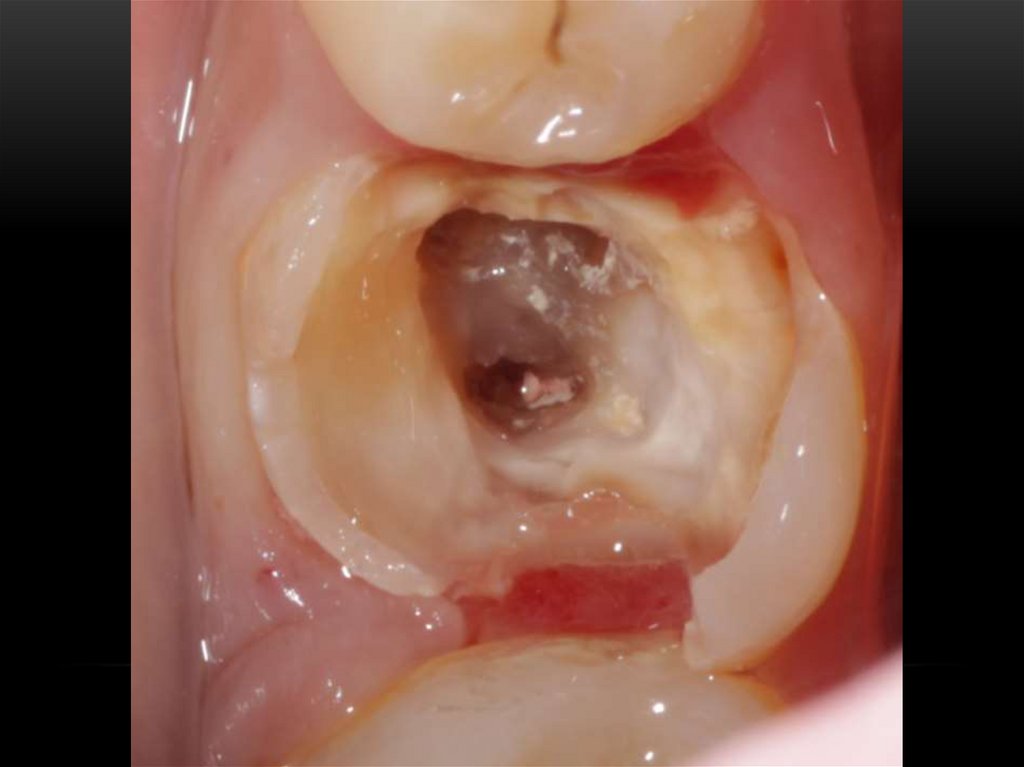

Лечение корневых каналов